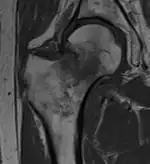

Typically, radiographs are taken of the hip from the front (AP view), and side (lateral view). Frog leg views are to be avoided, as they may cause severe pain and further displace the fracture.[5] In situations where a hip fracture is suspected but not obvious on x-ray, an MRI is the next test of choice. If an MRI is not available or the patient can not be placed into the scanner a CT may be used as a substitute. MRI sensitivity for radiographically occult fracture is greater than CT. Bone scan is another useful alternative however substantial drawbacks include decreased sensitivity, early false negative results, and decreased conspicuity of findings due to age related metabolic changes in the elderly.

A case demonstrating a possible order of imaging in initially subtle findings: